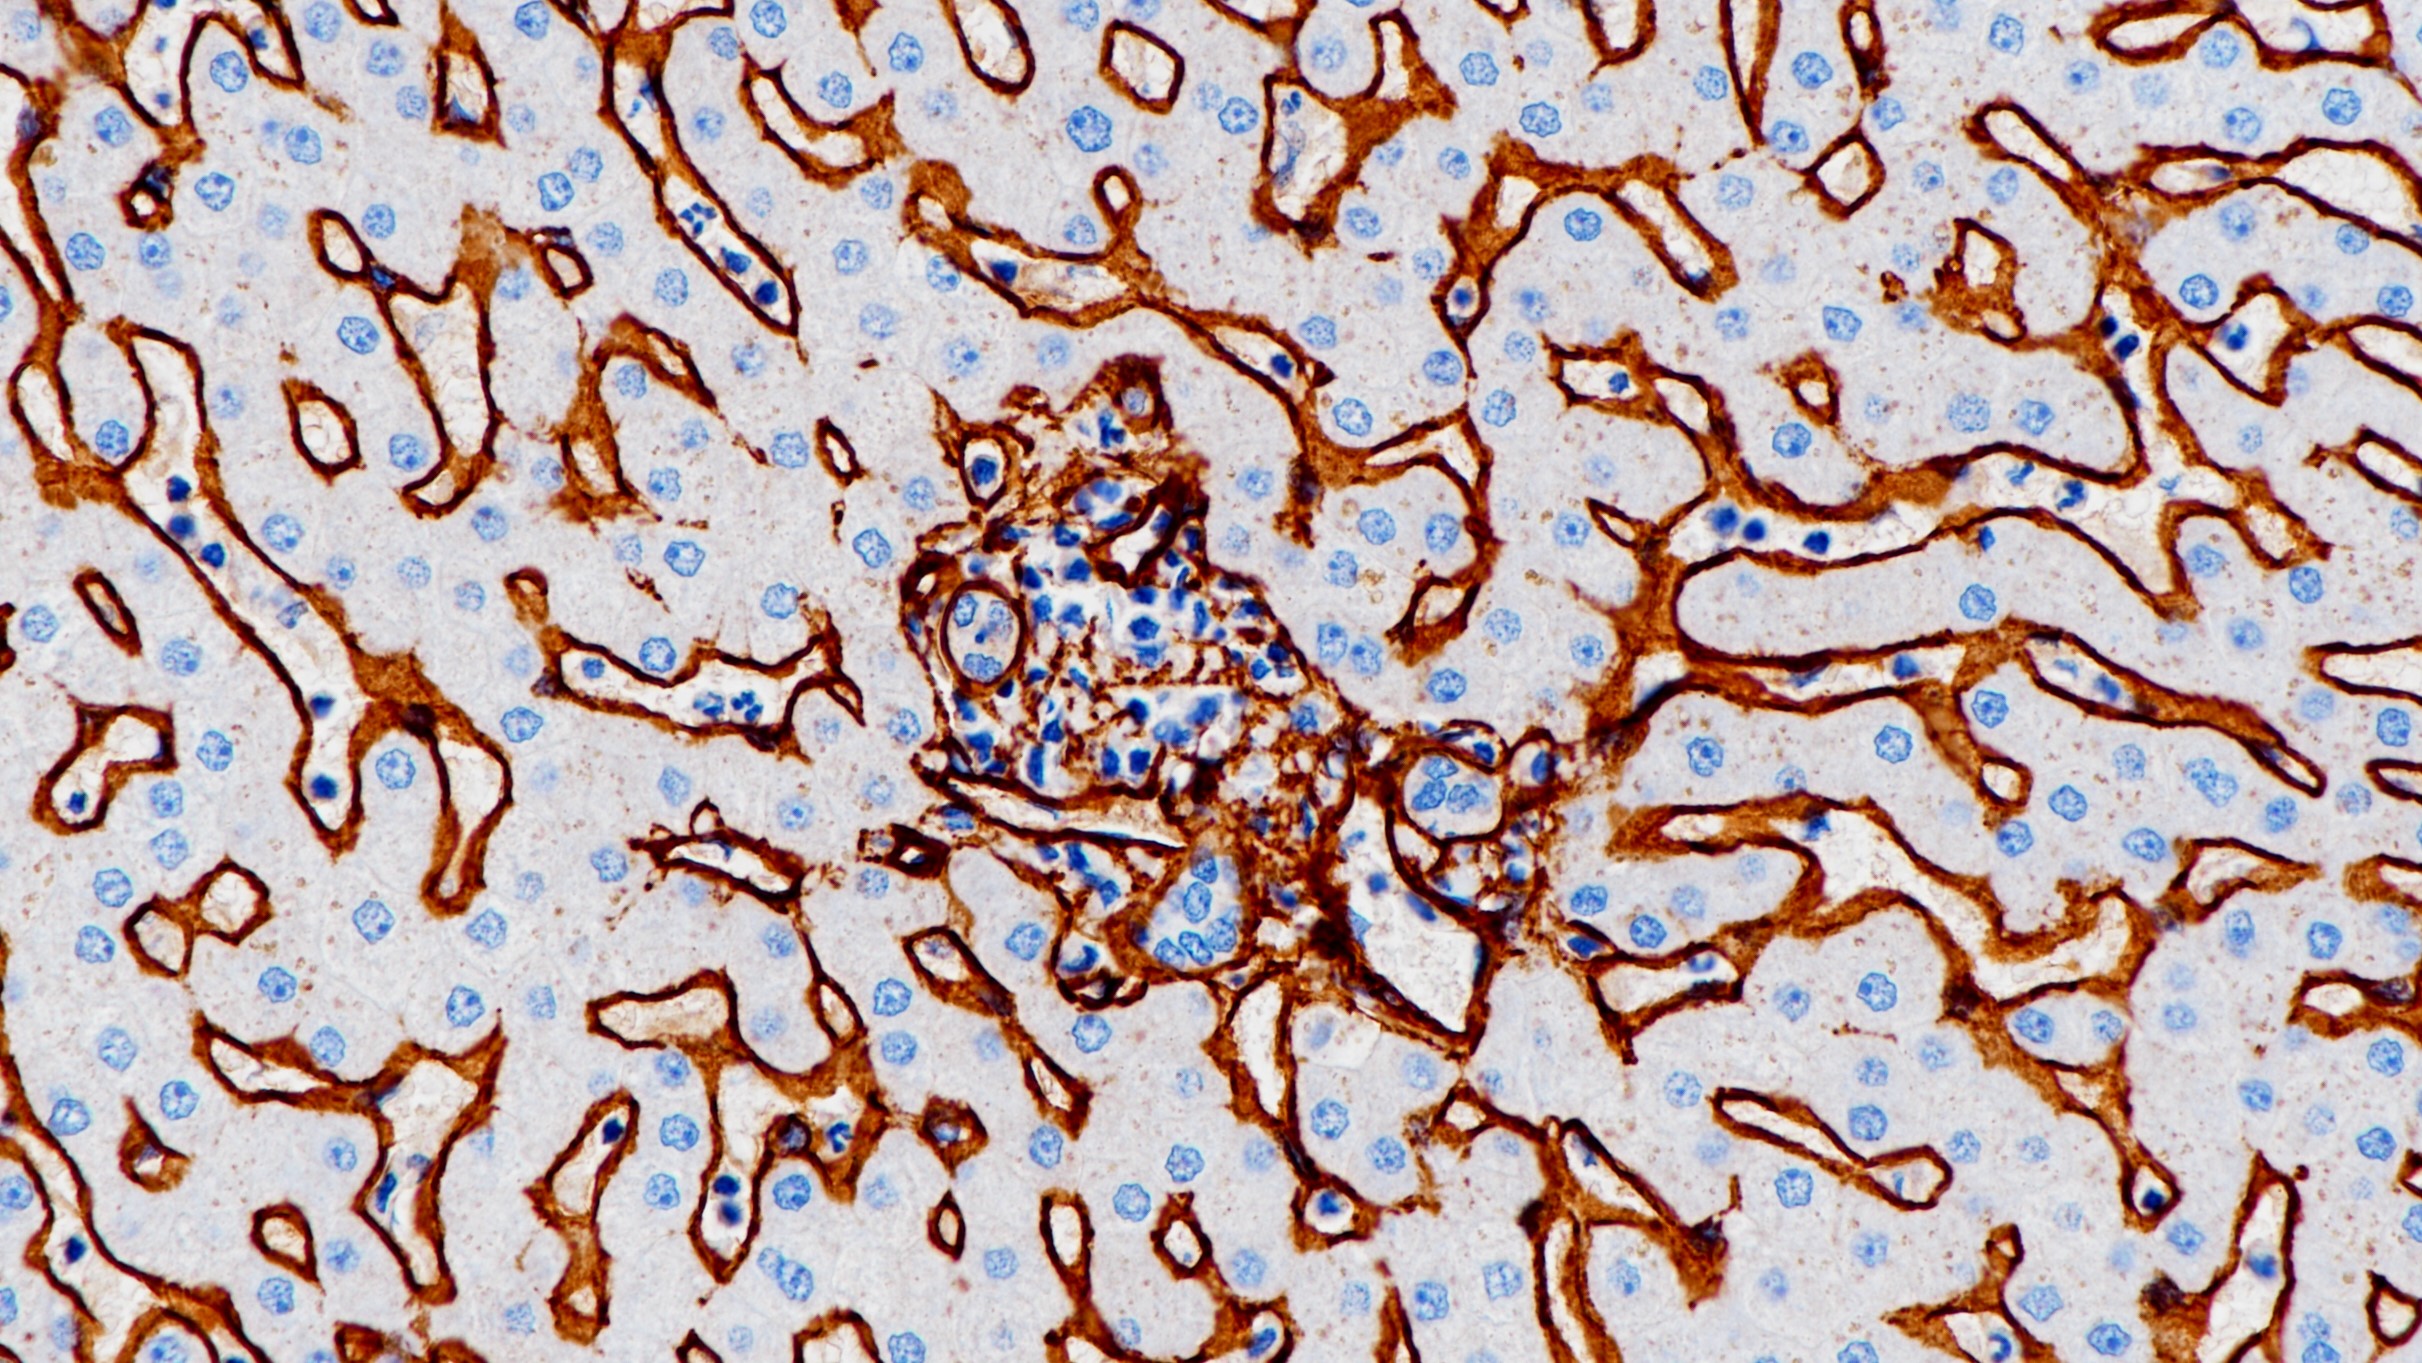

2.Expression of Olig2, Nestin, NogoA and AQP4 have no impact on overall survival in IDH-wildtype glioblastoma.[J]. Behling Felix,Barrantes-Freer Alonso,Behnes Carl Ludwig,Stockhammer Florian,Rohde Veit,Adel-Horowski Antonia,Rodríguez-Villagra Odir Antonio,Barboza Miguel Angel,Brück Wolfgang,Lehmann Ulrich,Stadelmann Christine,Hartmann Christian. PloS one. 2020(3)